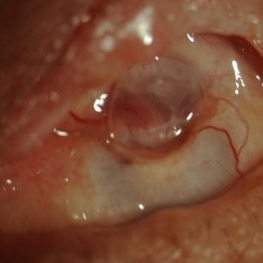

Panophthalmitis

Jul 12 2014 by Philip J. Polkinghorne, MD

A 85-year-old lady who presented with an eroding intraocular lens. She had been initially treated with herbal medicines which failed to control the infection.

Photographer: Philip Polkinghorne

Condition/keywords: cataract surgery, endophthalmitis, panophthalmitis